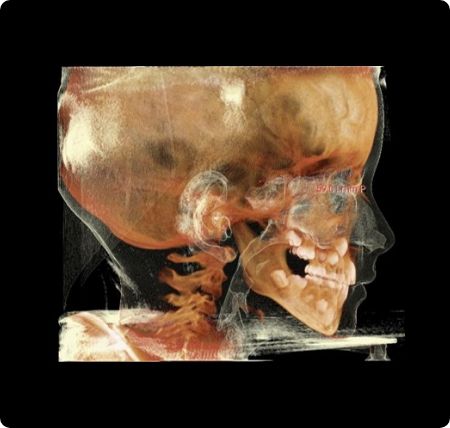

RAMPAによる気道容積の変化イメージ

三谷医師の開発から始まり、多くの経験を経て、現在ではその効果として歯並びはもちろんのこと、姿勢や鼻づまり、いびき、睡眠時無呼吸、喘息など、一見して歯並びとは関係のないことにも大きな改善が認められています。さらにお顔立ちにも変化が見られ、表情までもよくなっています。

審美よりむしろ、これら健康に関わることの方が、人生において、より大きな意義をもちます。実効的に骨格に関わり、結果が期待できるからこそ、RAMPAでは、このようなお伝えができます。